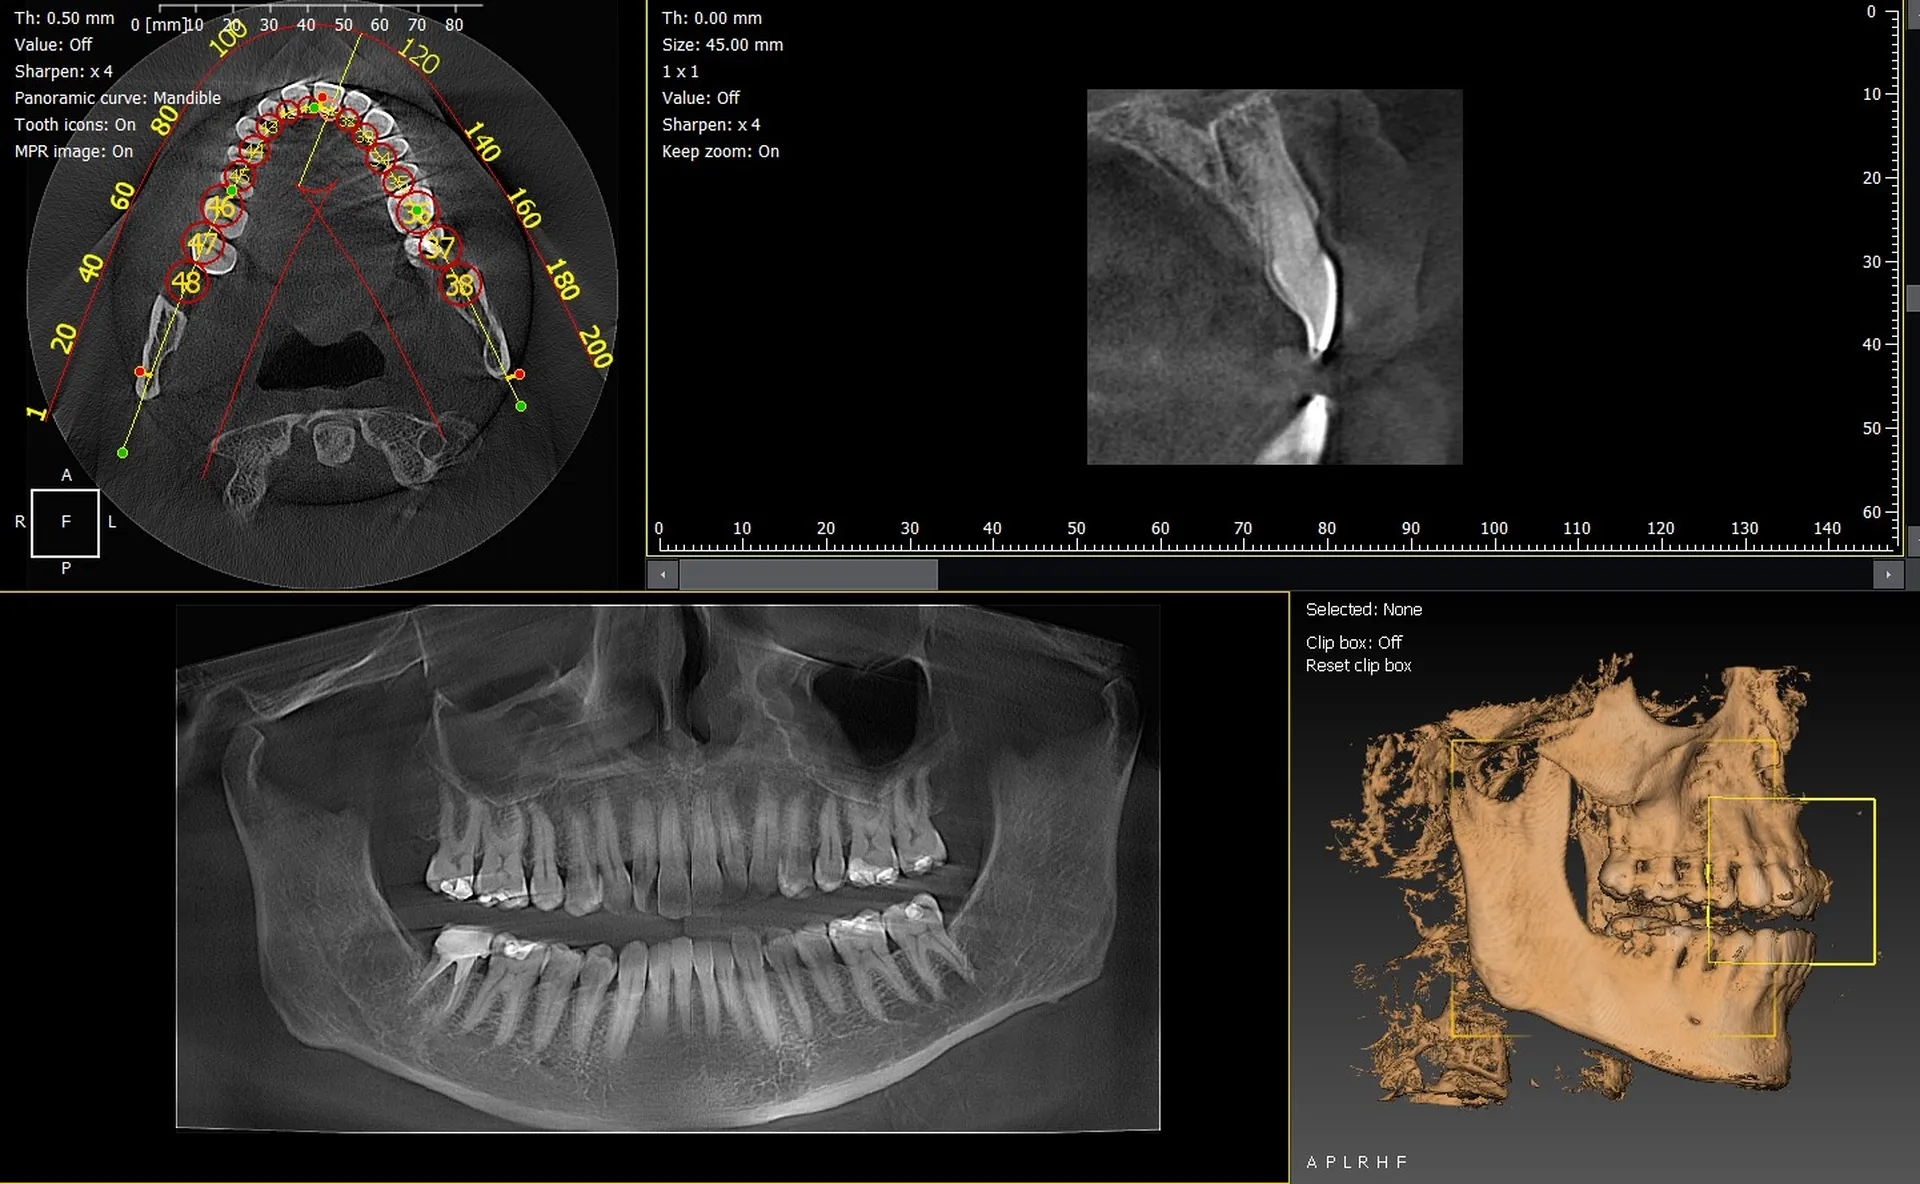

Les cabinets dentaires de Brignoles et du Var (83) modernisent leur plateau technique grâce à des solutions d’imagerie 3D performantes. Les panoramiques CBCT 3D VistaVox de Dürr Dental et Owandy I-Max 3D s’imposent comme des références, offrant une excellente qualité d’image et une précision diagnostique optimale.

VistaVox 3D : précision et champ optimisé

Le VistaVox se distingue par :

• un volume d’examen parfaitement adapté à l’arcade,

• une haute résolution idéale en implantologie et endodontie,

• une dose optimisée,

• un positionnement patient simple et rapide.